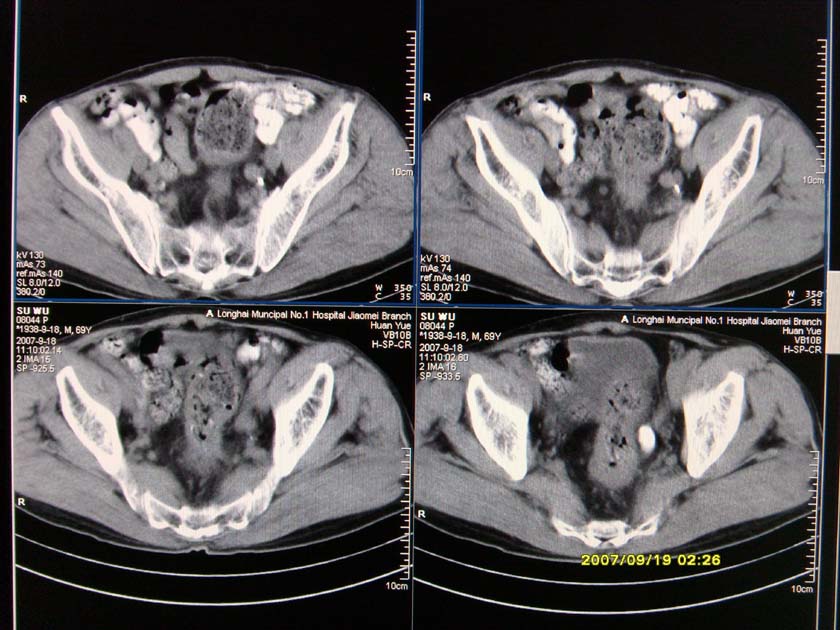

以下是引用xclzq_910在2007-9-19 16:58:00的发言:[br]直肠壁增厚,管腔偏移,直肠癌可能性大

以下是引用宝天曼在2007-9-19 21:11:00的发言:[br]根据直肠壁不规则增厚,考虑直肠肿瘤,不过最后的确诊还是需要肠镜.